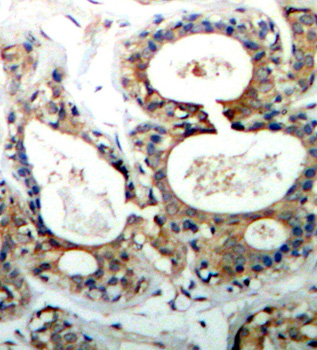

• AP0267: image 2

Immunohistochemical analysis of paraffin-embedded human breast carcinoma tissue using Phospho-PTPN11-Y542 antibody.